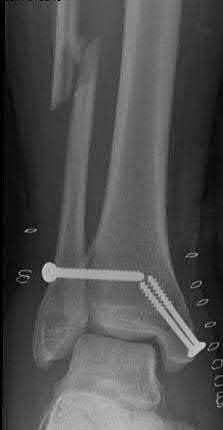

A 25-year-old male sustains an ankle fracture dislocation and undergoes open reduction and internal fixation. He returns to clinic five months following surgery complaining of continued ankle pain and instability with weight bearing. His immediate post-operative AP radiograph is seen in Figure A. Which of the following could have prevented this patient from developing persistent pain?

The patient presents with continued ankle pain and instability following open reduction and internal fixation. The radiograph in figure A demonstrates inadequate restoration of fibular length, likely leading to continued tibiotalar instability.

Illustration A demonstrates fibular malreduction with dislocation of the fibula anterior to the tibial incisura. Illustration B shows a comminuted fibula fracture along with a measurement of length from an intact fibula. The arc from the lateral process of the talus to the peroneal groove of the distal fibula is known as the "dime" sign and should remain unbroken if fibular length has been restored. Illustration C demonstrates the use of a push-pull screw and lamina spreader to regain length intraoperatively for a comminuted fibula fracture.